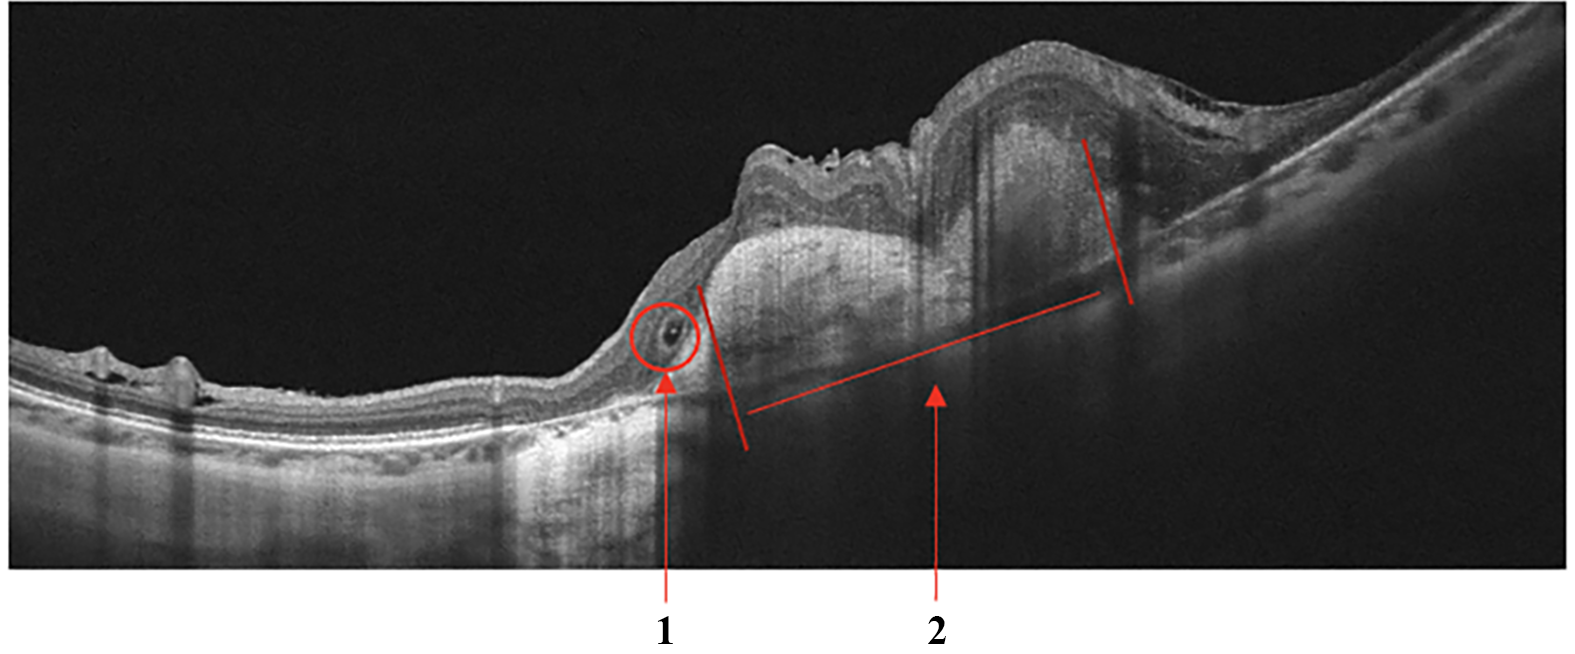

Retinal Vein Occlusion

Secondary ME is the leading cause of visual loss in patients with central retinal vein occlusion (CRVO). OCT is the critical imaging modality to diagnose and formulate a treatment plan for cystic macular edema (CME) of this etiology. In contrast to DME, the ME secondary to a branch or CRVO is generally cystic and localized to the inner retina following leakage from engorged veins, Fig.5a. OCT scans also show a higher level of hyperreflectivity of the inner retina due to ischemia. The long-term prognosis of vein occlusion will depend on the degree of ischaemic damage to the retinal tissue and the structural damage to the neural pathways after CME resorption. The presence and severity of any DRIL is an indicator of likely visual prognosis [35, 36].

Refer to caption

((a)) Retinal Vein Occlusion

((b)) Retinal Artery Occlusion

Figure 5: Retinal Vein Occlusion (RVO). Cystic macular edema in central retinal vein thrombosis. (a): 1 - Intraretinal fluid (IRF), 2 - hyperreflectivity of the inner retinal layers; Signs of Retinal Artery Occlusion (RAO) (a): 1 - Increased hyperreflectivity of the inner retina following ischemia, 2 - prominent middle limiting membrane (p-MLM).

Retinal Artery Occlusion

Occlusion of the central retinal artery (CRAO) and its branches (BRAO) leads to the formation of acute tissue ischemia, giving a specific OCT picture - pronounced hyperreflectivity, loss of homogeneity, and edema of the inner parts of the retina containing the ganglion cells, Fig.5b. Also, a biomarker of acute ischemia is a prominent middle limiting membrane (p-MLM) - a hyperreflective line or band located in the inner part of the outer plexiform layer at the border with the outer nuclear layer. It is not ordinarily visible, which appears in the early period of the pathological damage and is due to opacification of the middle retinal layers [37].